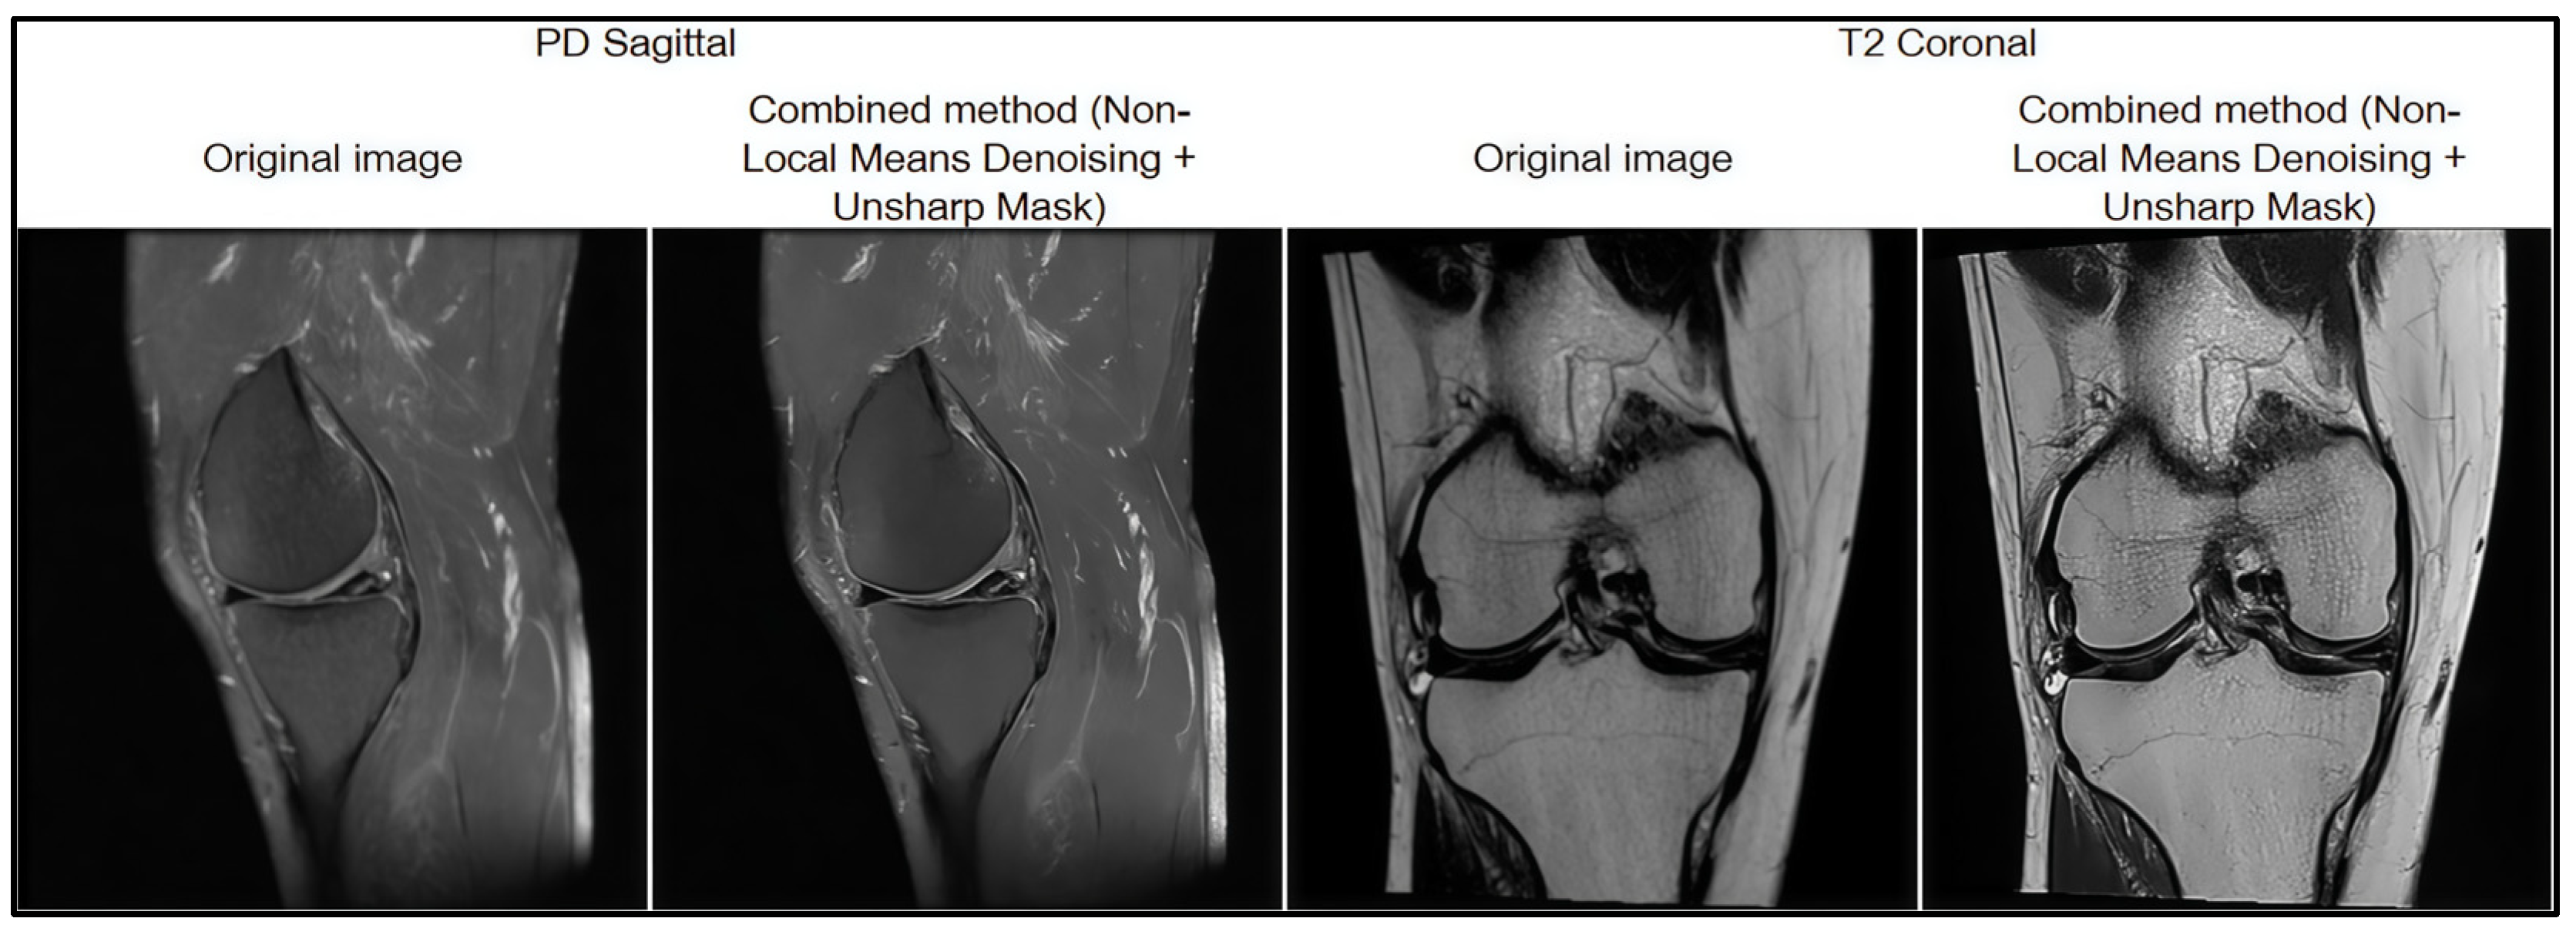

Based on the results of the comparative analysis, the combined approach of Non-Local Means Denoising and Unsharp Mask was selected, as it demonstrated the best quantitative performance (MSE = 32.55; PSNR = 41.37; SSIM = 0.92), indicating its high effectiveness in MRI image preprocessing. In addition, this method produced the most visually satisfactory results, achieving optimal noise suppression while preserving anatomical boundaries (Figure 5).

Figure 5.

Result of filtration preprocessing.